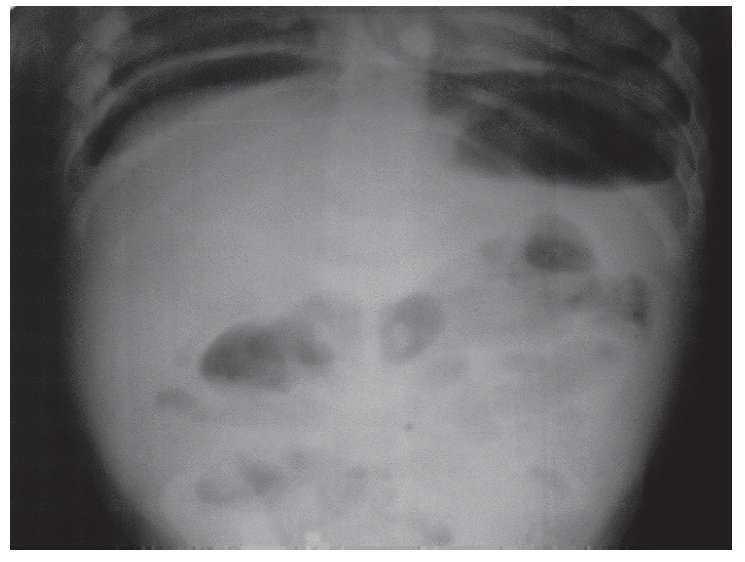

De inmediato la menor fue puesta en condiciones y trasladada a sala de operaciones en donde se le realizó laparotomía exploradora. Durante el procedimiento se encontró rotura de íleon terminal, a 30 cm de la válvula ileocecal, de 0.5 cm, en su borde antimesentérico. Además, había peritonitis generalizada y la presencia de un botón imantado (Imagen 2). Se le efectuó reparación primaria, limpieza y colocación de un drenaje de caucho. Tres días después, se observó salida de líquido intestinal por la canalización, por lo que fue necesario llevarla nuevamente a quirófano encontrándose otra perforación en ciego. Se realizó reparación primaria. La evolución posterior fue satisfactoria y se dio de alta 5 días después.

Imagen 2. Se muestra el momento durante el acto operatorio en que es extraído el botón magnetizado del interior del intestino de la menor.